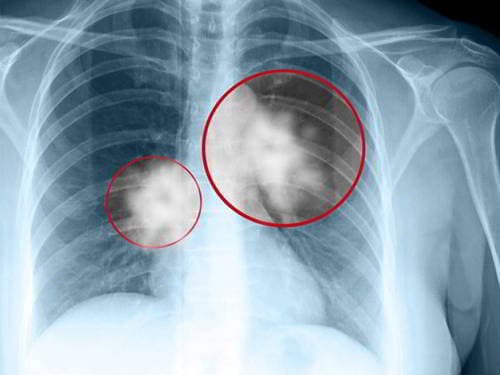

Như đã khẳng định u phổi có nguy hiểm không phụ thuộc vào tính chất khối u.Đối với u phổi lành tính, thường không có triệu chứng, chỉ được tình cơ phát hiện qua chụp X quang phổi. U mô thừa là loại u phổi lành tính thường gặp nhất. Các u xơ, u mỡ, u cơ trơn, u mạch máu… cũng khá phổ biến. Trường hợp bệnh nhân xác định u phổi lành tính nhưng không có bất kì biểu hiện nào, không ảnh hưởng đến sức khỏe đôi khi chỉ cần theo dõi khối u.

Khác với u phổi lành tính, ung thư phổi cực kì nguy hiểm. Bệnh có thể đe dọa trực tiếp đến tính mạng người bệnh nếu không được phát hiện sớm và tiến hành điều trị kịp thời.